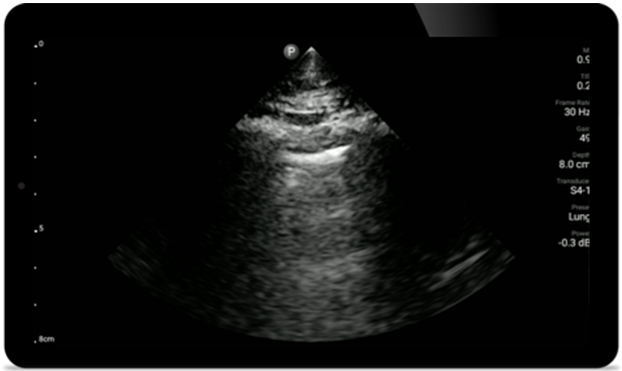

Utilice Lumify para la evaluación de las vías respiratorias y pulmonares

Las soluciones Lumify POCUS pueden ayudarle a detectar el tubo endotraqueal dentro de la tráquea, ayudar en los procedimientos de cricotirotomía emergentes, en el diagnóstico de derrame pleural y enfermedades alveolares intersticiales.